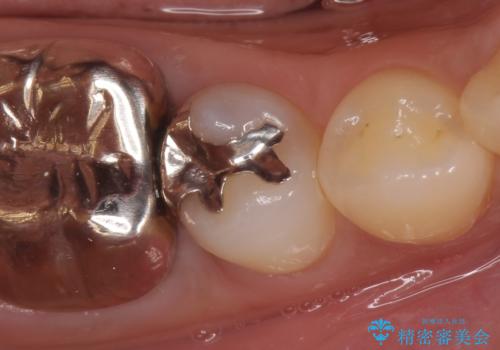

- 右下5番目の歯がしみるといらっしゃった方の症例です。

銀歯及び虫歯を除去し、適合に優れたPGA(ゴールド)インレーにて修復を行いました。